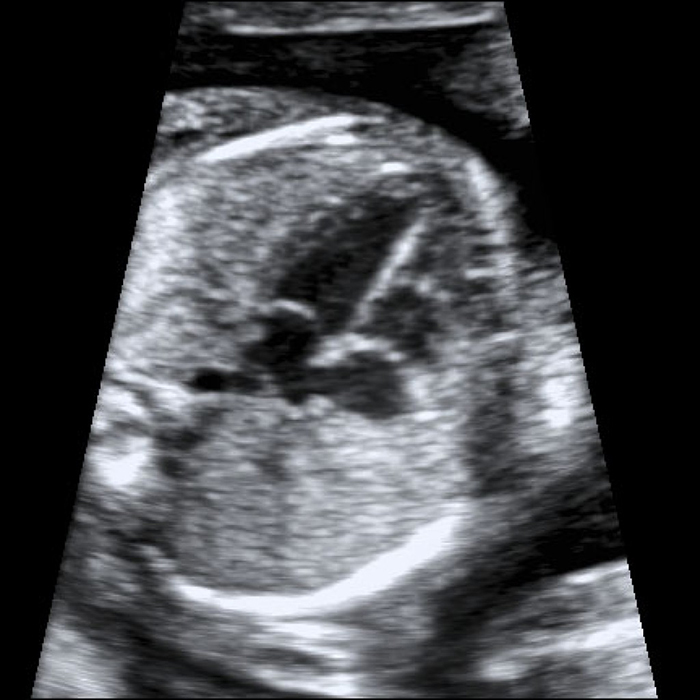

Las cardiopatías congénitas son las malformaciones que más se presentan los recién nacidos (en 1/125 neonatos, 0.8-1%). El 50% de las cardiopatías congénitas se consideran defectos mayores, presentan una mortalidad global del 25-35%, se asociación a otras malformaciones en un 20%, y a las cromosomopatías en un 20-40% por lo que presentan una alta mortalidad neonatal (25-35%). Por todo ello una evaluación adecuada en la ecografía morfológica es necesaria y fundamental y ante la presencia de una sospecha de patología o de la presencia de un marcador de posible cardiopatía se debe realizar lo que se llama una ecocardiografía morfológica y funcional fetal

En nuestro servicio esta exploración se realiza con ecógrafos de gama alta y por personal especializado en este tipo de ecografía, con la finalidad de obtener un diagnostico prenatal acertado que nos facilite un asesoramiento de este tipo de patología fetal.